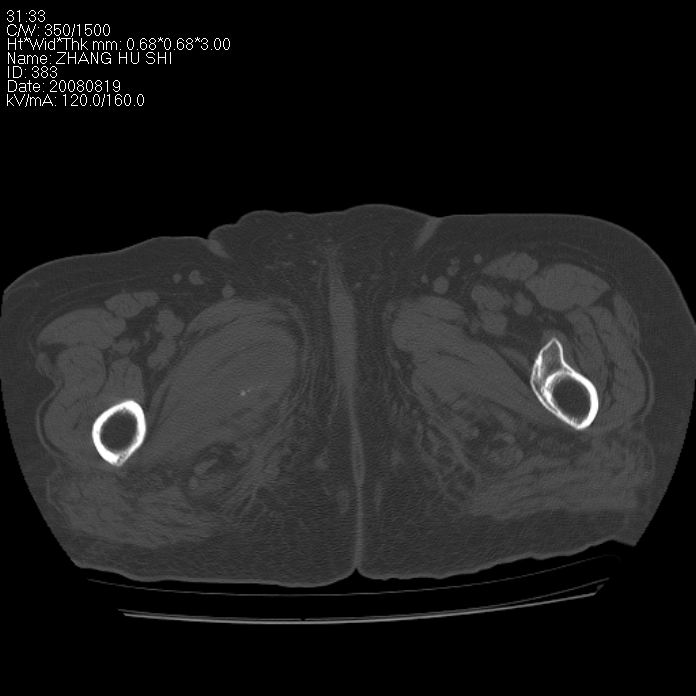

标题: CT15287:女 93岁 右髋关节疼痛 原左侧粗隆间骨折 CT发现右耻 [打印本页]

标题: CT15287:女 93岁 右髋关节疼痛 原左侧粗隆间骨折 CT发现右耻

支持转移

支持转移并周围软组织侵犯右闭孔内肌侵犯,但tb不能完全除外。

耻骨软骨肉瘤可能性大